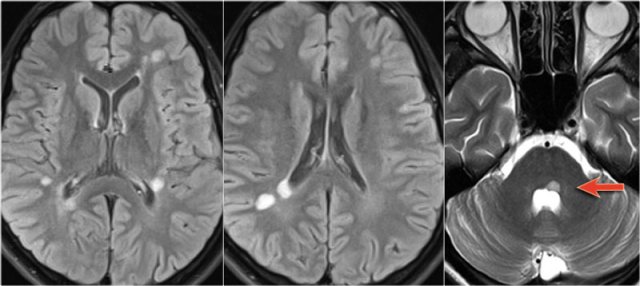

In another patient there are non-specific lesions in the cord.

Based on the examination of the spine alone, we have a broad differential diagnosis.

However when we examine the brain, it becomes obvious that we are dealing with MS.

In this case the findings in the brain are very helpful.

The location of the lesions is very typical: pons, periventricular and subcortical.